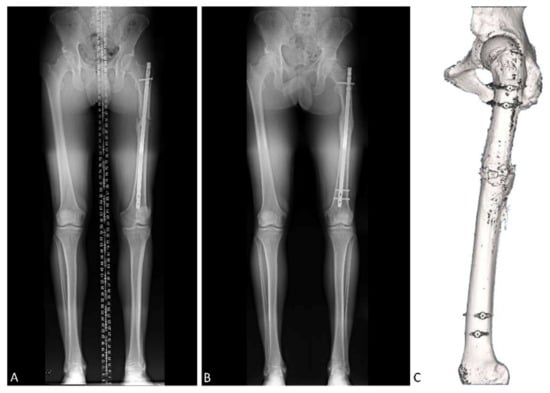

| Patient 1 | Patient 2 | Patient 3 | Patient 4 | Patient 5 | Patient 6 | |

|---|---|---|---|---|---|---|

| Age (years) | 23 | 72 | 40 | 30 | 59 | 35 |

| Sex | Female | Male | Male | Male | Female | Male |

| Side | Left | Left | Left | Right | Right | Left |

| Previous distal femur deformity | Internal rotation | External rotation | External rotation | Internal rotation | External rotation | Internal rotation |

| Pre-angulation (°) | −60 | 40 | 43 | −44 | 1 | −24 |

| Correction (°) | 45 | 50 | 50 | 33 | 15 | 19 |

| Post-angulation (ª) | −15 | −10 | −7 | −11 | −14 | −5 |